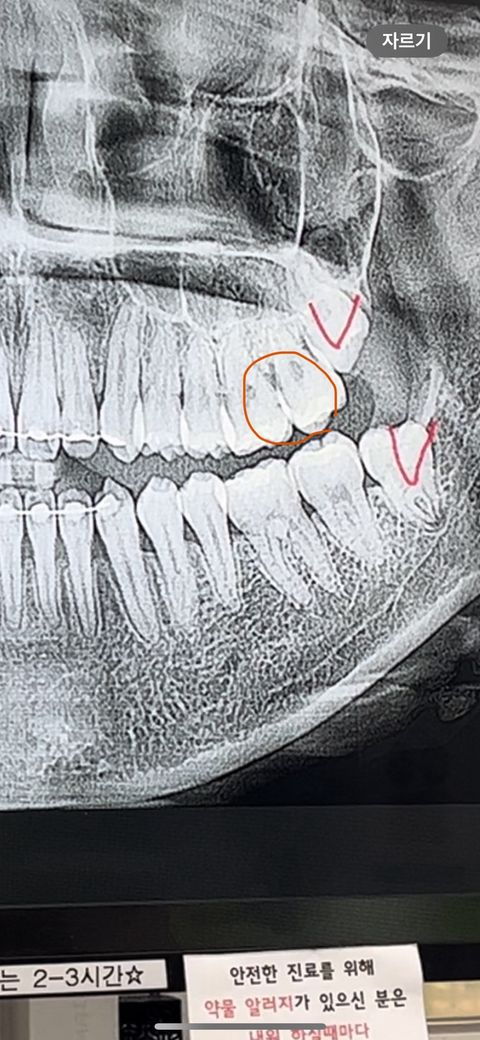

안녕하세요! 사진에 동그라미 친 부분에 검은 점 같은게 충치인지 궁금해서 올려봅니다 혹시 충치라면 신경치료 해야하는지도 여쭤보고 싶습니다

충치보다는 방사선사진상 디펙트, 왜곡같습니다 겹쳐서 그렇게 보이고요 충치가 있다해도 신경치료할정도는 아닙니다